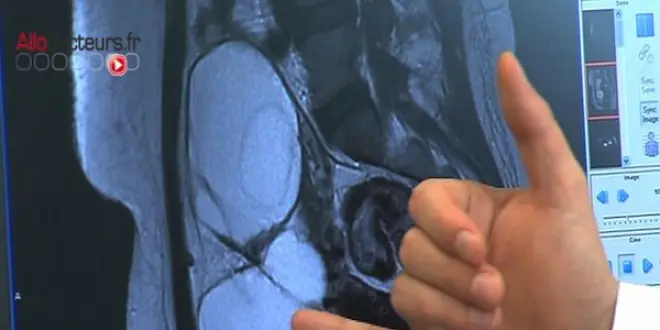

La tumeur de dix centimètres de large a été découverte lorsque la jeune Japonaise a subi une intervention chirurgicale pour enlever son appendice, selon la revue Neuropathology. Lorsque les médecins ont coupé la tumeur, ils ont trouvé des touffes de poils à l'intérieur, et une structure cérébrale de 3 centimètres de large recouverte d'une mince plaque d'os du crâne.

L’étude révèle qu'il s'agissait d'une sorte de petit cervelet, qui se trouve habituellement sous les deux hémisphères du cerveau. Une masse sur un côté ressemblait à une tige du cerveau, la structure qui normalement se joint à la moelle épinière.